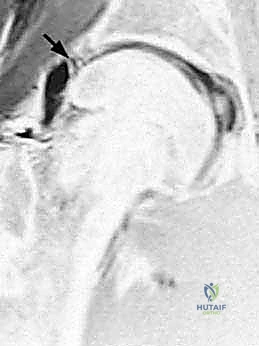

- الرنين المغناطيسي مع الصبغة المفصلية (MR Arthrogram): وهو المعيار الذهبي لتشخيص تمزقات الشفا الحقي وتلف الغضاريف. يتم حقن صبغة داخل المفصل قبل التصوير لإبراز أي تسرب للصبغة عبر التمزقات.